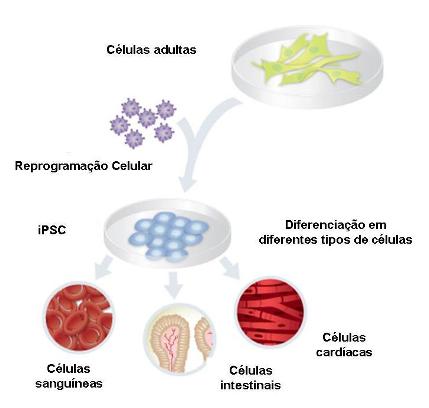

Recentemente foi descrita a criação de células estaminais pluripotentes induzidas (iPSC, induced pluripotent stem cells) a partir de células adultas humanas, através da expressão forçada de fatores de transcrição definidos como essenciais para a manutenção do estado de pluripotência das células estaminais embrionárias. De acordo com os últimos dados, as iPSC possuem propriedades de auto-renovação e de pluripotência semelhantes às células estaminais embrionárias, e foram já diferenciadas in vitro com sucesso em vários tipos celulares (Figura 3). Assim, a reprogramação de iPSC permite a obtenção de células com as propriedades únicas das células estaminais embrionárias, a partir de células diferenciadas adultas do próprio paciente. Esta abordagem, mostra-se promissora para futuras terapias celulares, tendo despertado a atenção generalizada de investigadores e médicos.

Figura 3 – Diferenciação de células adultas em vários tipos celulares através da reprogramação de células estaminais pluripotentes.